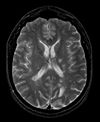

Registration Results

Unregistered baseline data: PD vs. T1Gd Unregistered baseline data: PD vs. T1Gd

Unregistered followup data: PD exam 2 vs. exam 1 Unregistered followup data: PD exam 2 vs. exam 1

Registered baseline data Registered baseline data

Registered followup data Registered followup data